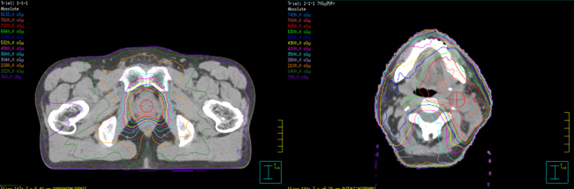

1)強度変調放射線治療(IMRT)

多方向から強度を調整した放射線を照射し、病変に放射線を集中させることと周囲の正常臓器への放射線を抑えることを両立させ、副作用を抑えながら病変へより高線量を集中させることのできる治療です。当院ではVMAT(強度変調回転照射)というIMRTの応用型を用いており、照射ビームを変調させながら照射ヘッドを回転させることで治療時間の短縮を図っています。